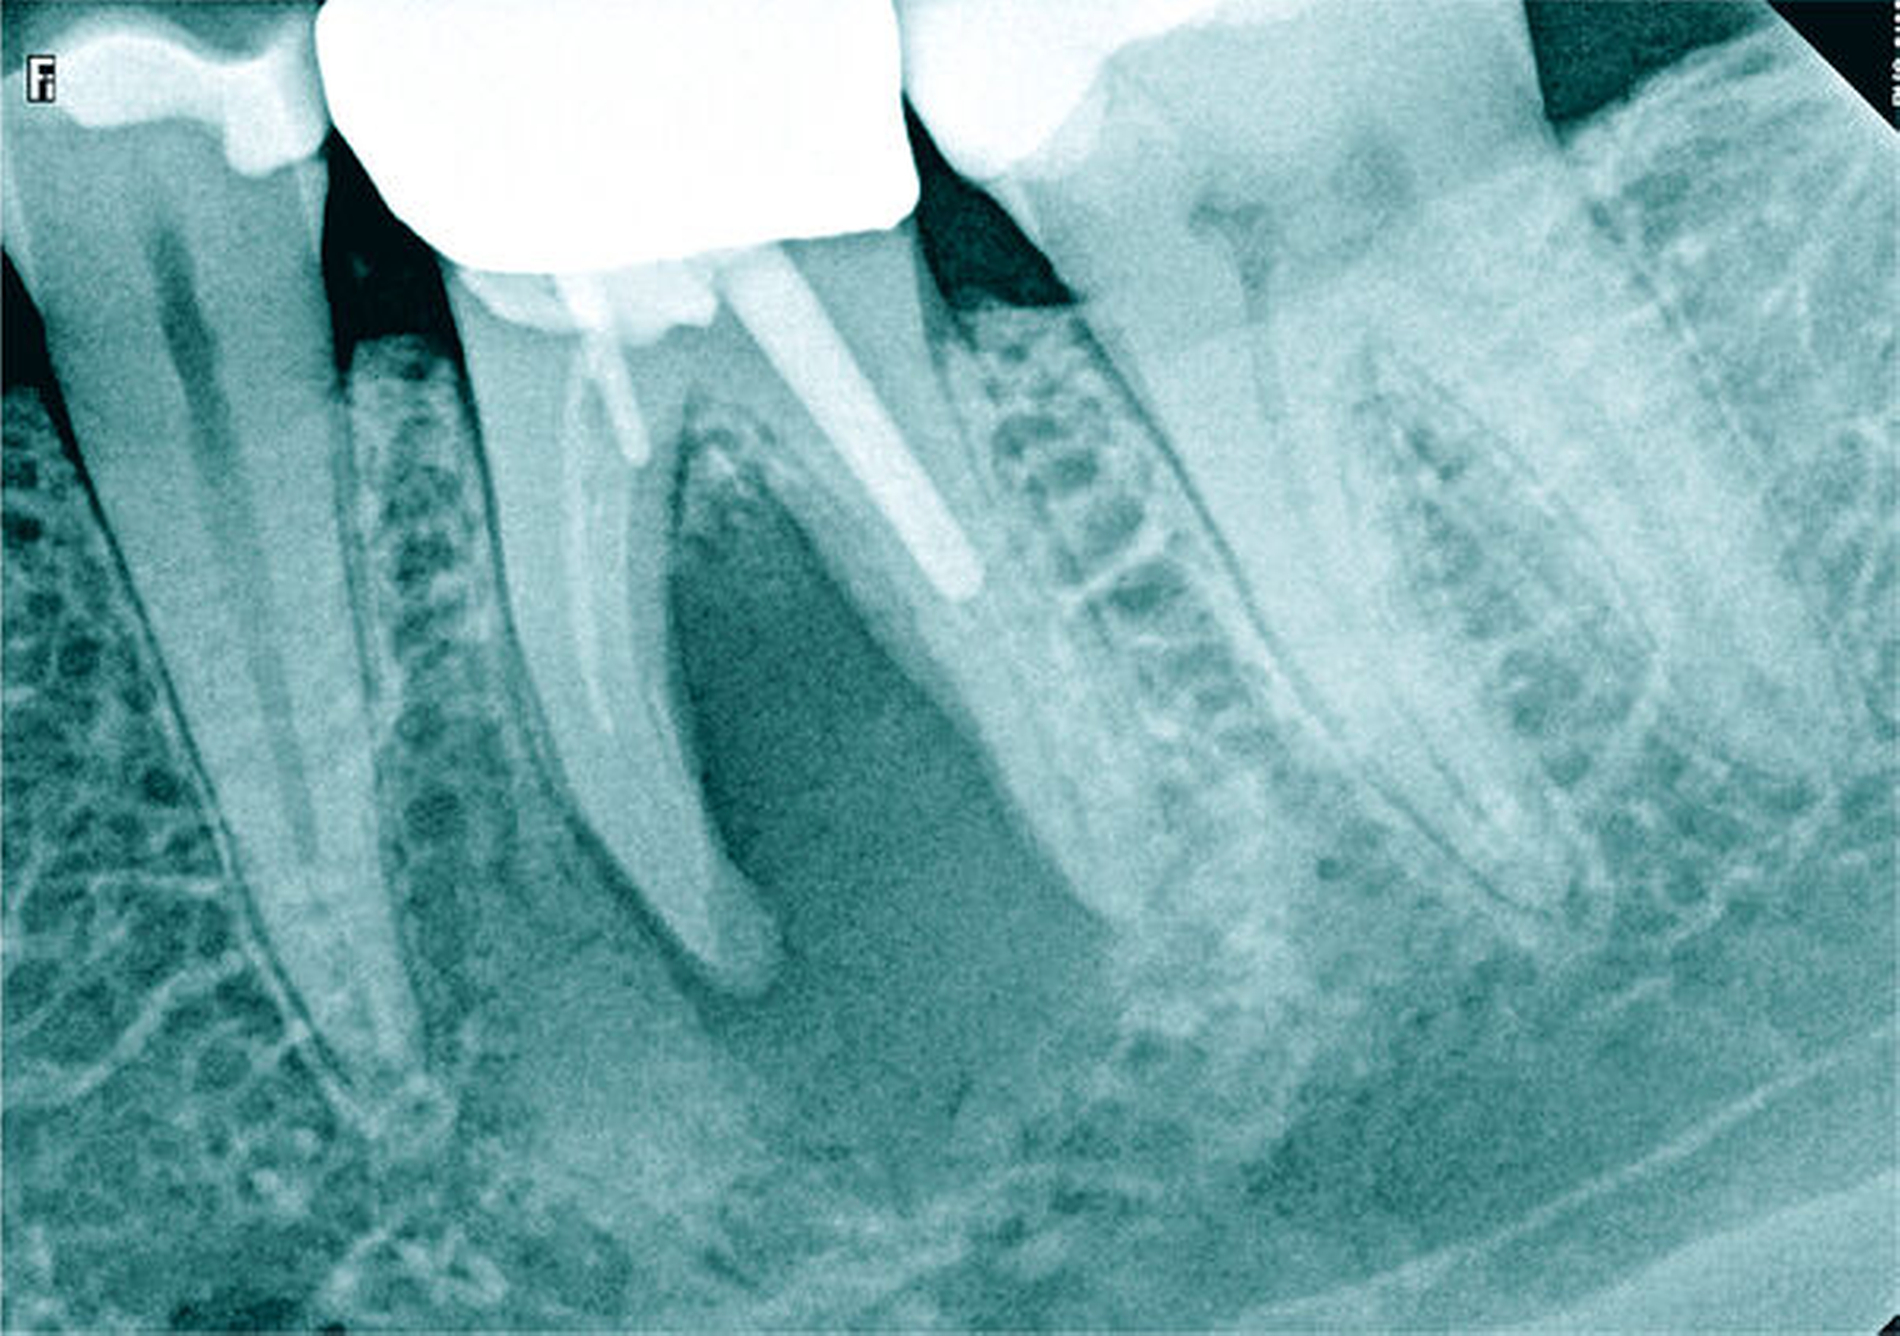

Auf der intraoralen Röntgenaufnahme lagen eine unvollständige Wurzelkanalfüllung und eine apikale Aufhellung am Zahn 45 vor. Apikal ist auf der Röntgenaufnahme kein Wurzelkanal erkennbar. Die zu kurze Wurzelkanalfüllung deutete auf eine apikale Blockade von eingepresstem Debris oder eine Stufenpräparation hin (Abbildung 14). Als seltene anatomische Variation war eine apikale Aufteilung in zwei Wurzelkanäle in Betracht zu ziehen, so dass die Nutzung einer optischen Vergrößerung mit koaxialer Lichtzufuhr als Hilfsmittel empfehlenswert erschien. Die apikale Wurzelkrümmung ließ einen gleichmäßigen großen Krümmungsradius vermuten. Bei lateralen Aufhellungen ist mit einem lateralen Foramen apicale oder einer Wurzelkanalaufteilung zu rechnen, so dass in diesem Fall die apikale Erweiterung und der Verschluss eine sehr hohe Schwierigkeit vermuten lassen.

Die Differenzialdiagnostik und die Therapie unterlagen erwartungsgemäß dem sehr hohen Schwierigkeitsgrad. Es wurde eine dentinadhäsive Aufbaufüllung mit Restauration des fehlenden Kontaktpunkts bei subgingivaler Lage des Füllungsrandes erforderlich und zusätzlich musste die apikale Blockade minimalinvasiv mit modernen endodontischen Hilfsmitteln eliminiert werden. Die Entfernung der alten Wurzelkanalfüllung gelang in der Kombination von Handinstrumenten und rotierenden NiTi-Feilen (Abbildungen 15a und 15b). Unter Sicht mit dem Dentalmikroskop konnte die intrakanaläre Blockade mit Ultraschall und vorgebogenen Feilen überwunden und thermoplastisch verschlossen werden, so dass bereits sechs Monate nach Therapieabschluss die apikale Aufhellung und klinische Schmerzsymptomatik abgeklungen waren (Abbildung 15c).